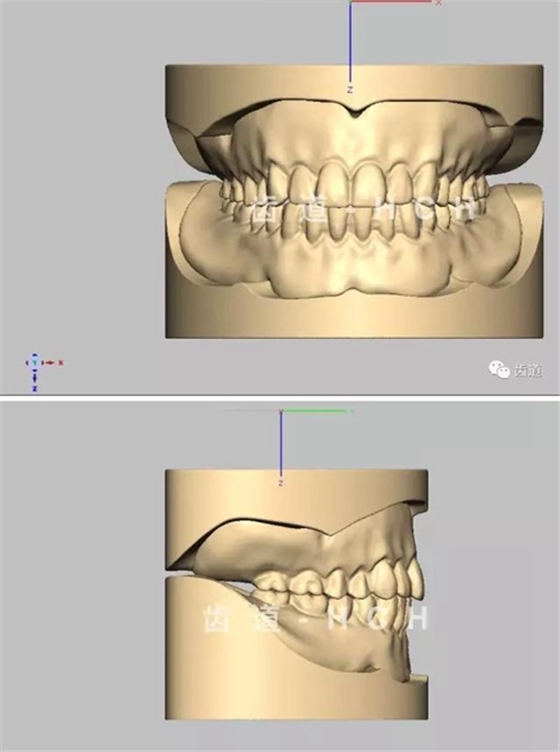

標(biāo)準(zhǔn)全口義齒模型截圖 科貿(mào)嘉友收錄